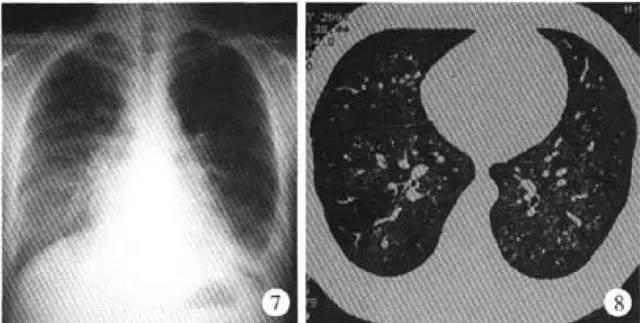

基本病史:患者女性,34 岁,间断性咳嗽、咯血伴气短 10 年,加重 2 周。患者 10 年前受凉后出现咳嗽、咳痰,痰中带血,伴有胸闷气短,严重时出血口唇紫绀。行影像学检查结果如下:

图 2 胸部 X 线正位片显示双肺弥漫分布的细小结节影,以双下肺为著,右侧较左侧重,左肋膈角变钝;胸部 CT 结果显示双下肺方腺泡样小结节影,右中叶可有。最终病理诊断结果为特发性肺含铁血黄色沉着症